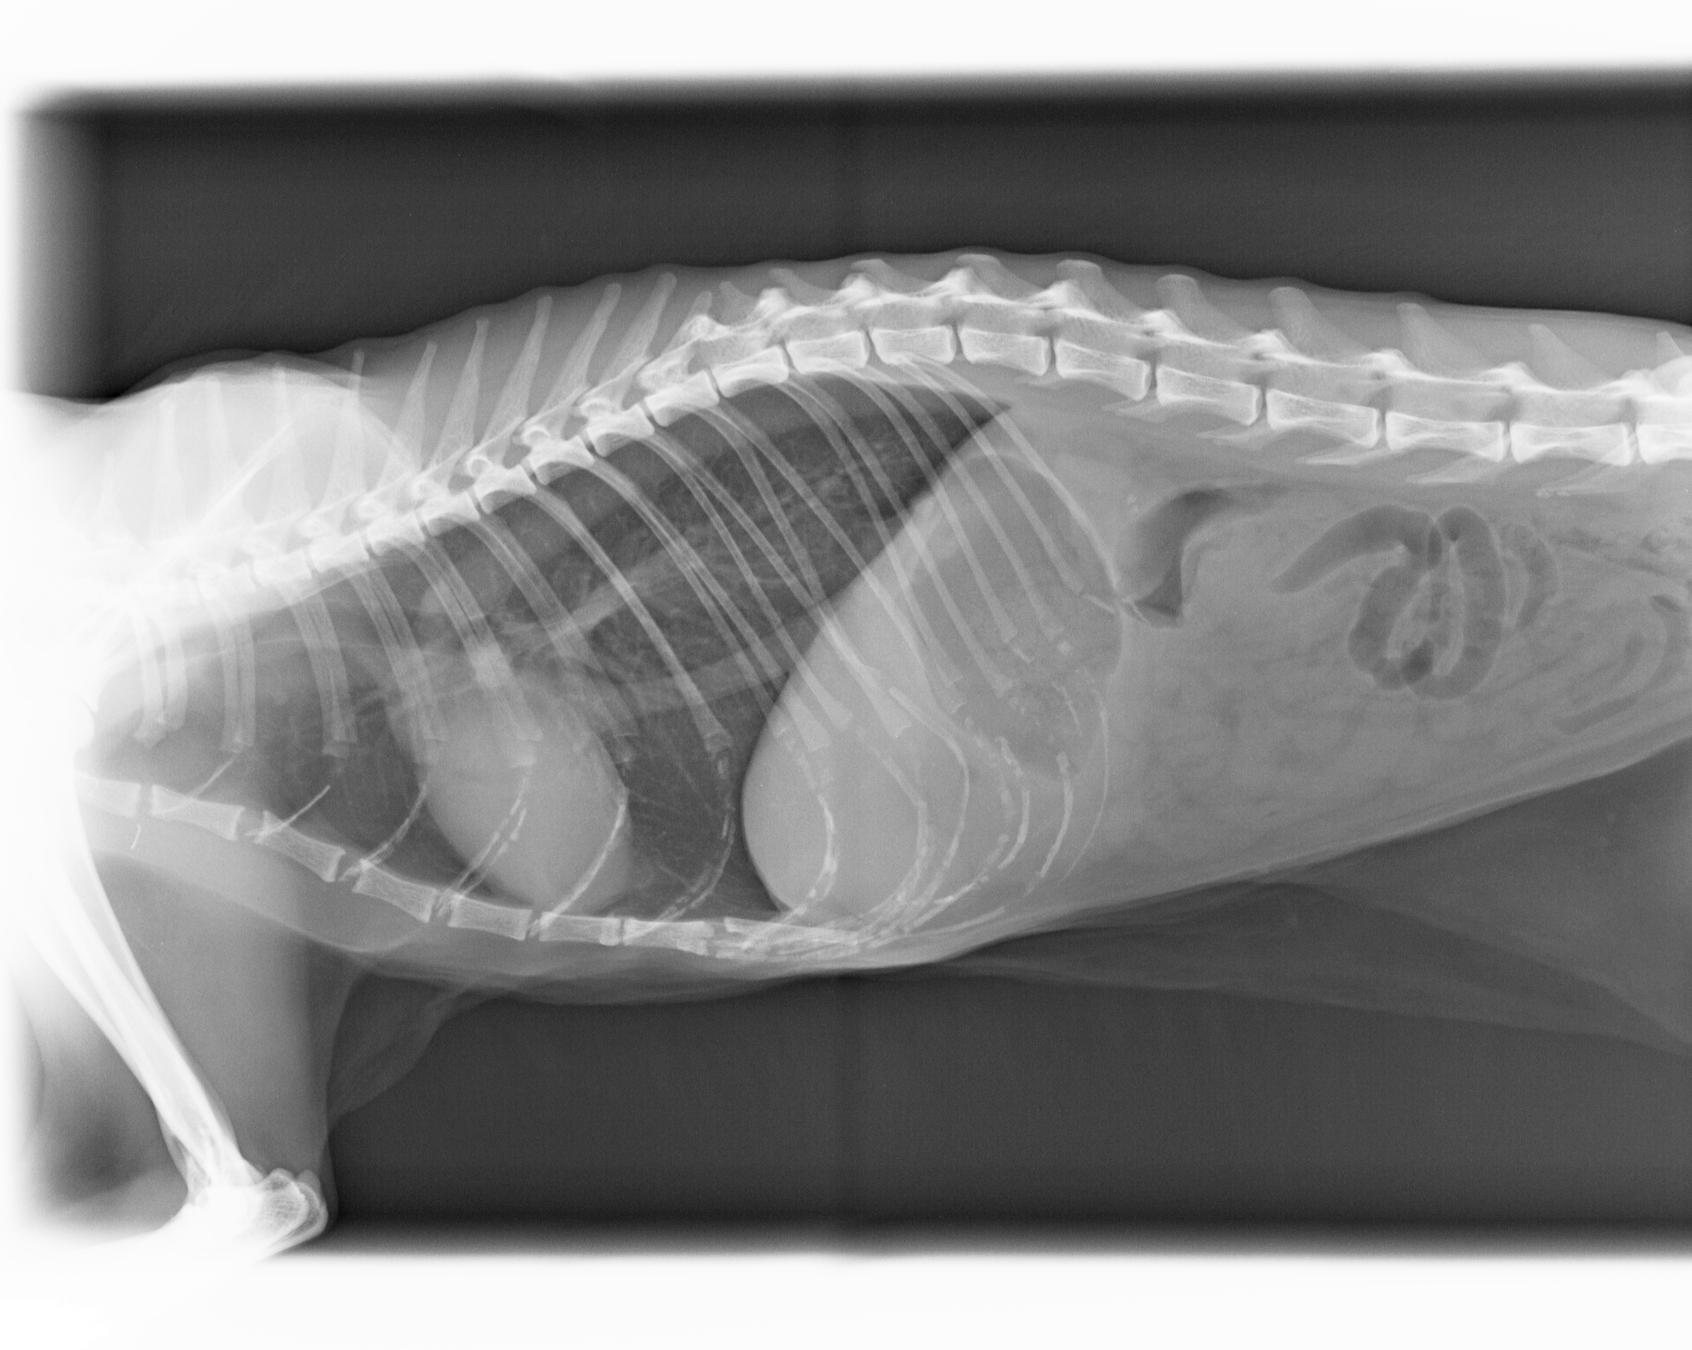

Radiologie Numérique

L'appareil de radiologie oriente le diagnostic en matière d'orthopédie ( os), en pneumologie et en médecine interne .

Le développement numérique assisté par ordinateur

facilite le diagnostic en retravaillant l 'image par informatique. Le client repart avec son cliché radio sur sa boite email.